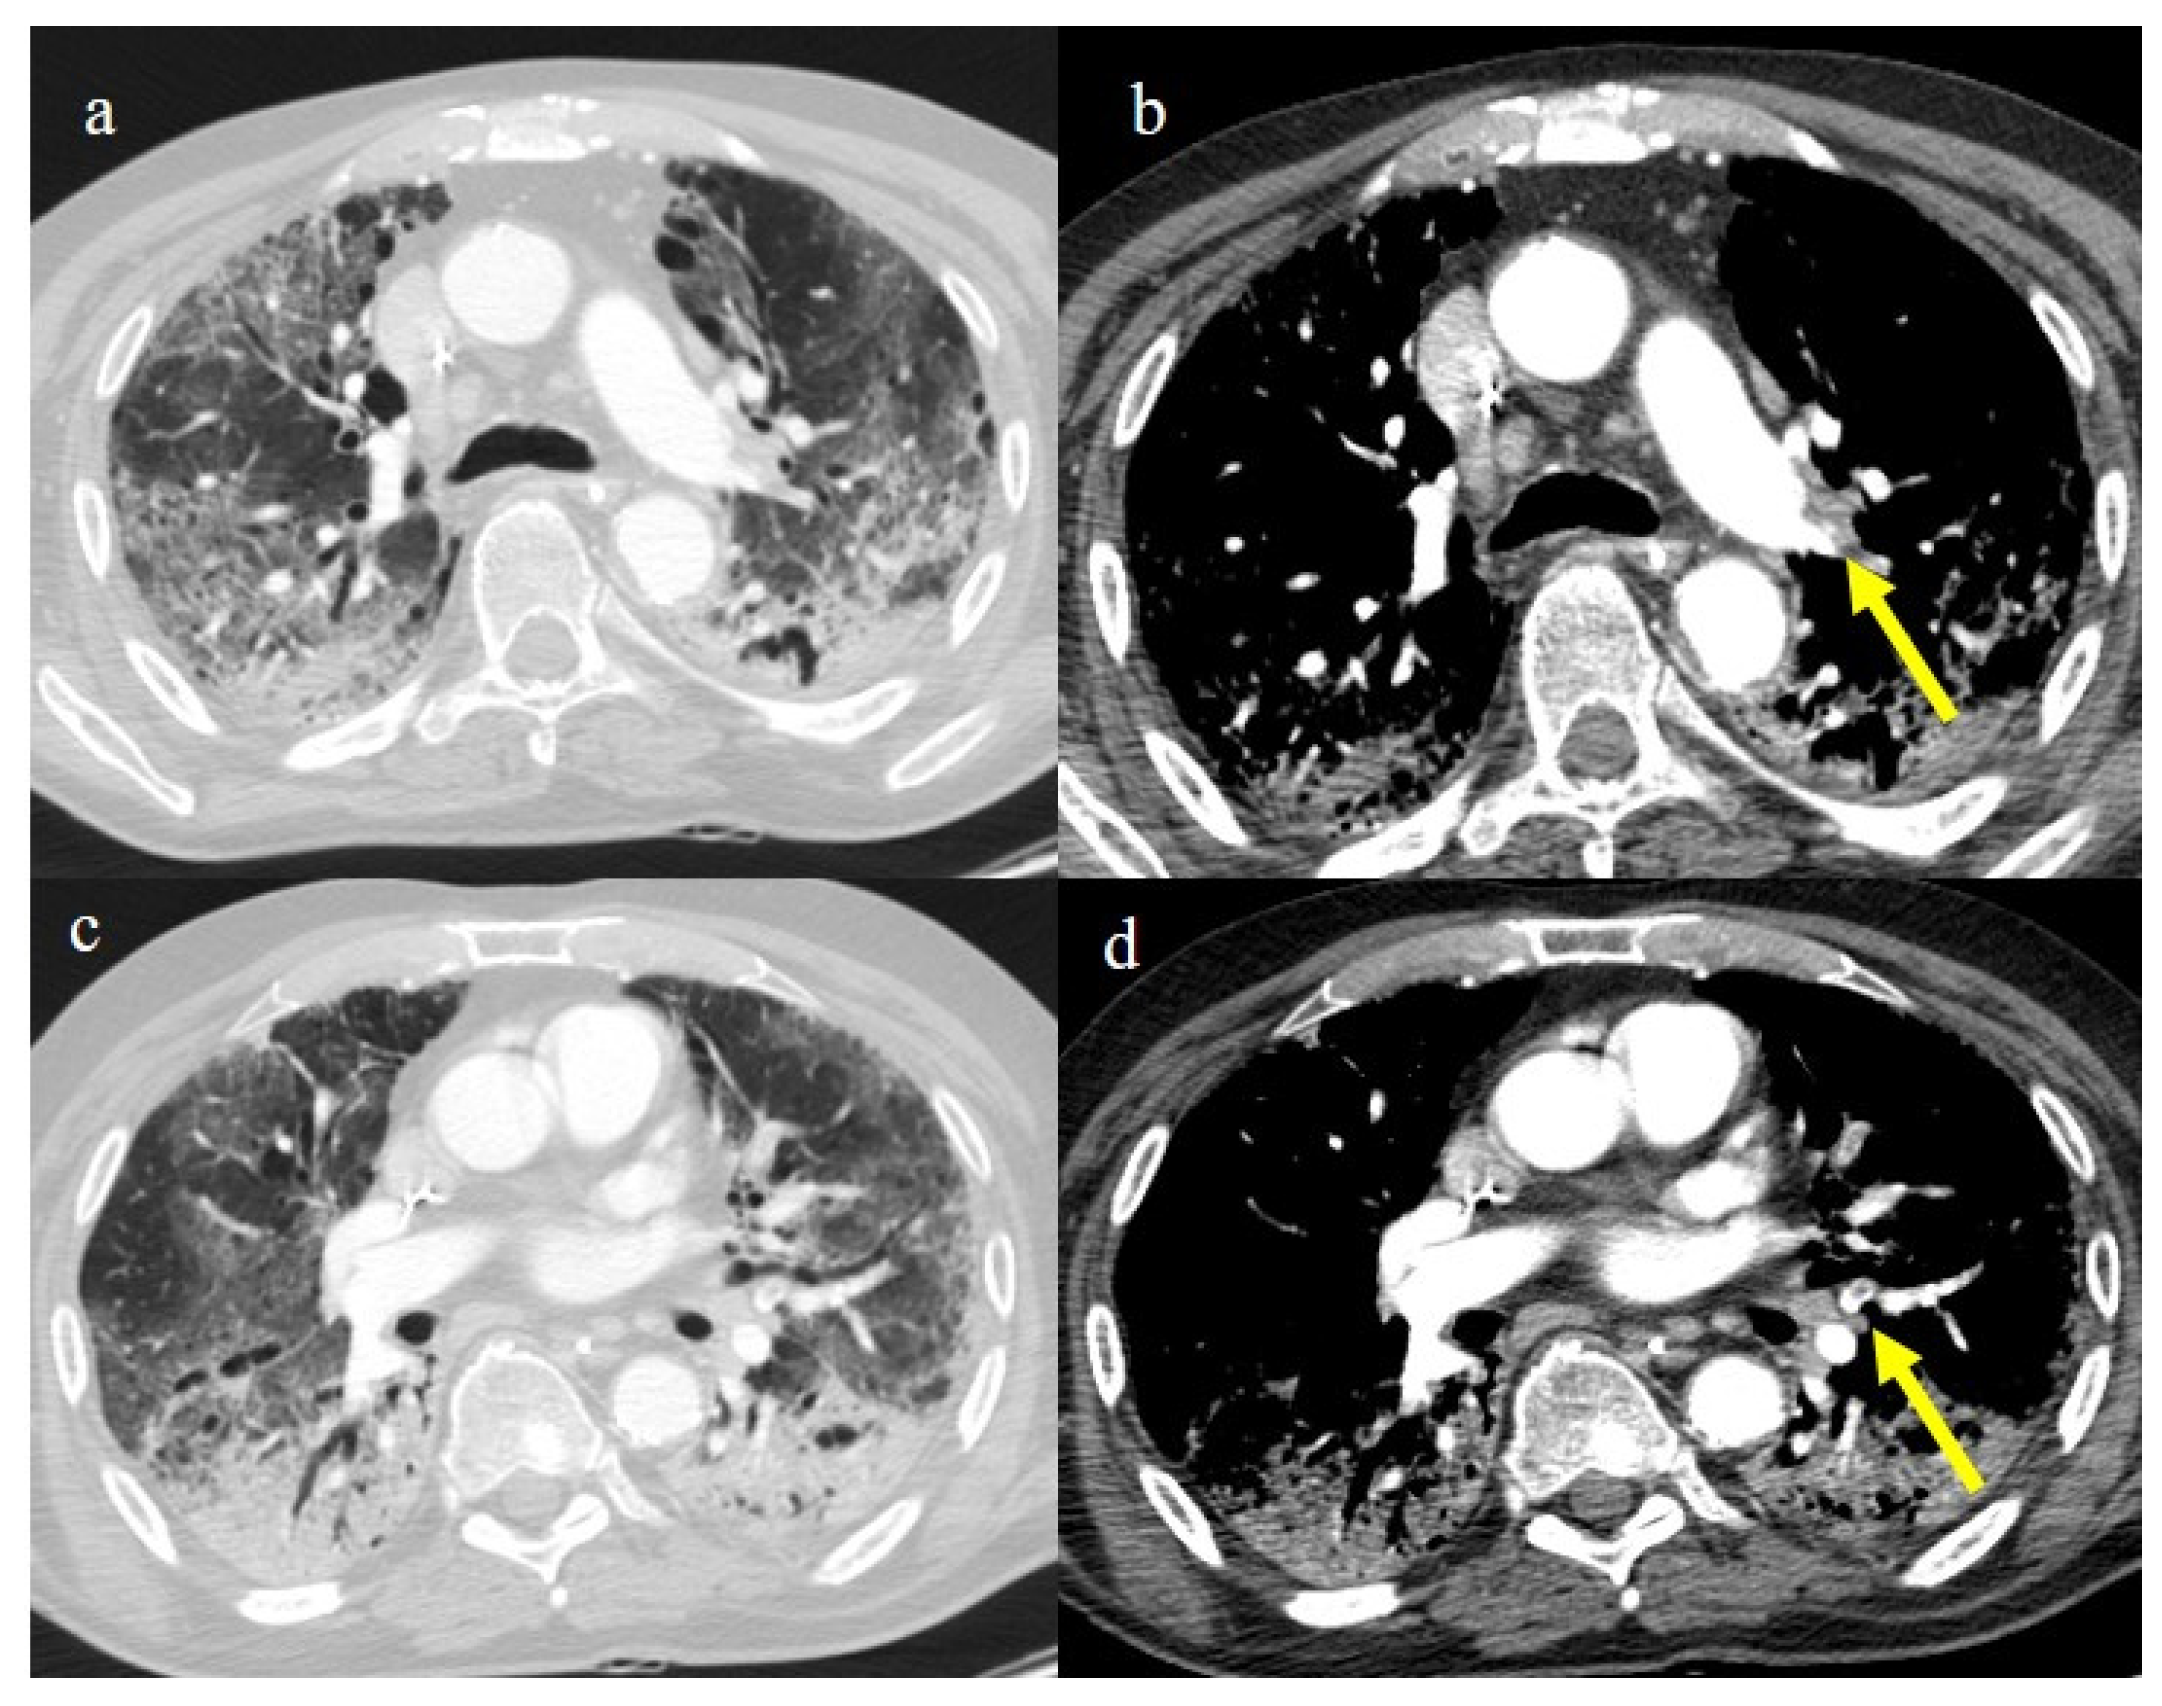

| Typical Appearance | GGOs with a crazy-paving pattern and consolidations in a peripheral and posterior or central-peripheral distribution; multilobar involvement; vascular enlargement, the halo and reversed halo sign; subpleural and parenchymal bands; and architectural distortion. They were predominant since the Delta wave. |

| Indeterminate Appearance | GGOs and consolidations with a unilateral, central, or upper-lobe distribution. |

| Atypical Appearance | Lobar consolidation, lung nodules or masses, miliary patterns, tree-in-bud patterns, cavitation, pleural effusion, central distribution, and lymphadenopathy. Atypical appearances were predominant during the Omicron waves. |

| Typical appearance | From the wild-type to the Delta variant. | Askani et al., 2022 [67] | The Delta variant presented more frequent typical features with more extensive lung involvement than the Omicron variant. The Omicron variant was more frequently associated with the absence of pneumonia. |

| Inui et al., 2021 [68] | Typical findings were characteristic of the wild type to the Delta variant. GGOs with consolidation and repair changes were more frequent in the Delta variant. The Delta variant also showed more rapid pneumonia progression than the wild-type and Alpha variants. | ||

| Ito et al., 2022 [54] | Peripheral GGO distributions were more frequent in the Alpha and Delta variants than the Omicron variant. | ||

| Kirka et al., 2022 [27] | Typical features were found in 40.8% of patients with the wild-type variant and 1.7% of patients with the Omicron variant. | ||

| Lee et al., 2023 [28] | Typical CT patterns were more frequent in the Delta group (76%) than in those with the Omicron variant (42%). | ||

| Yang et al., 2022 [78] | Of patients with the Alpha variant, 86.84% presented typical COVID-19 pneumonia CT features. | ||

| Yoon et al., 2023 [69] | Only 32% of patients with the Omicron variant presented typical findings, compared with 57% of the Delta variant cases. | ||